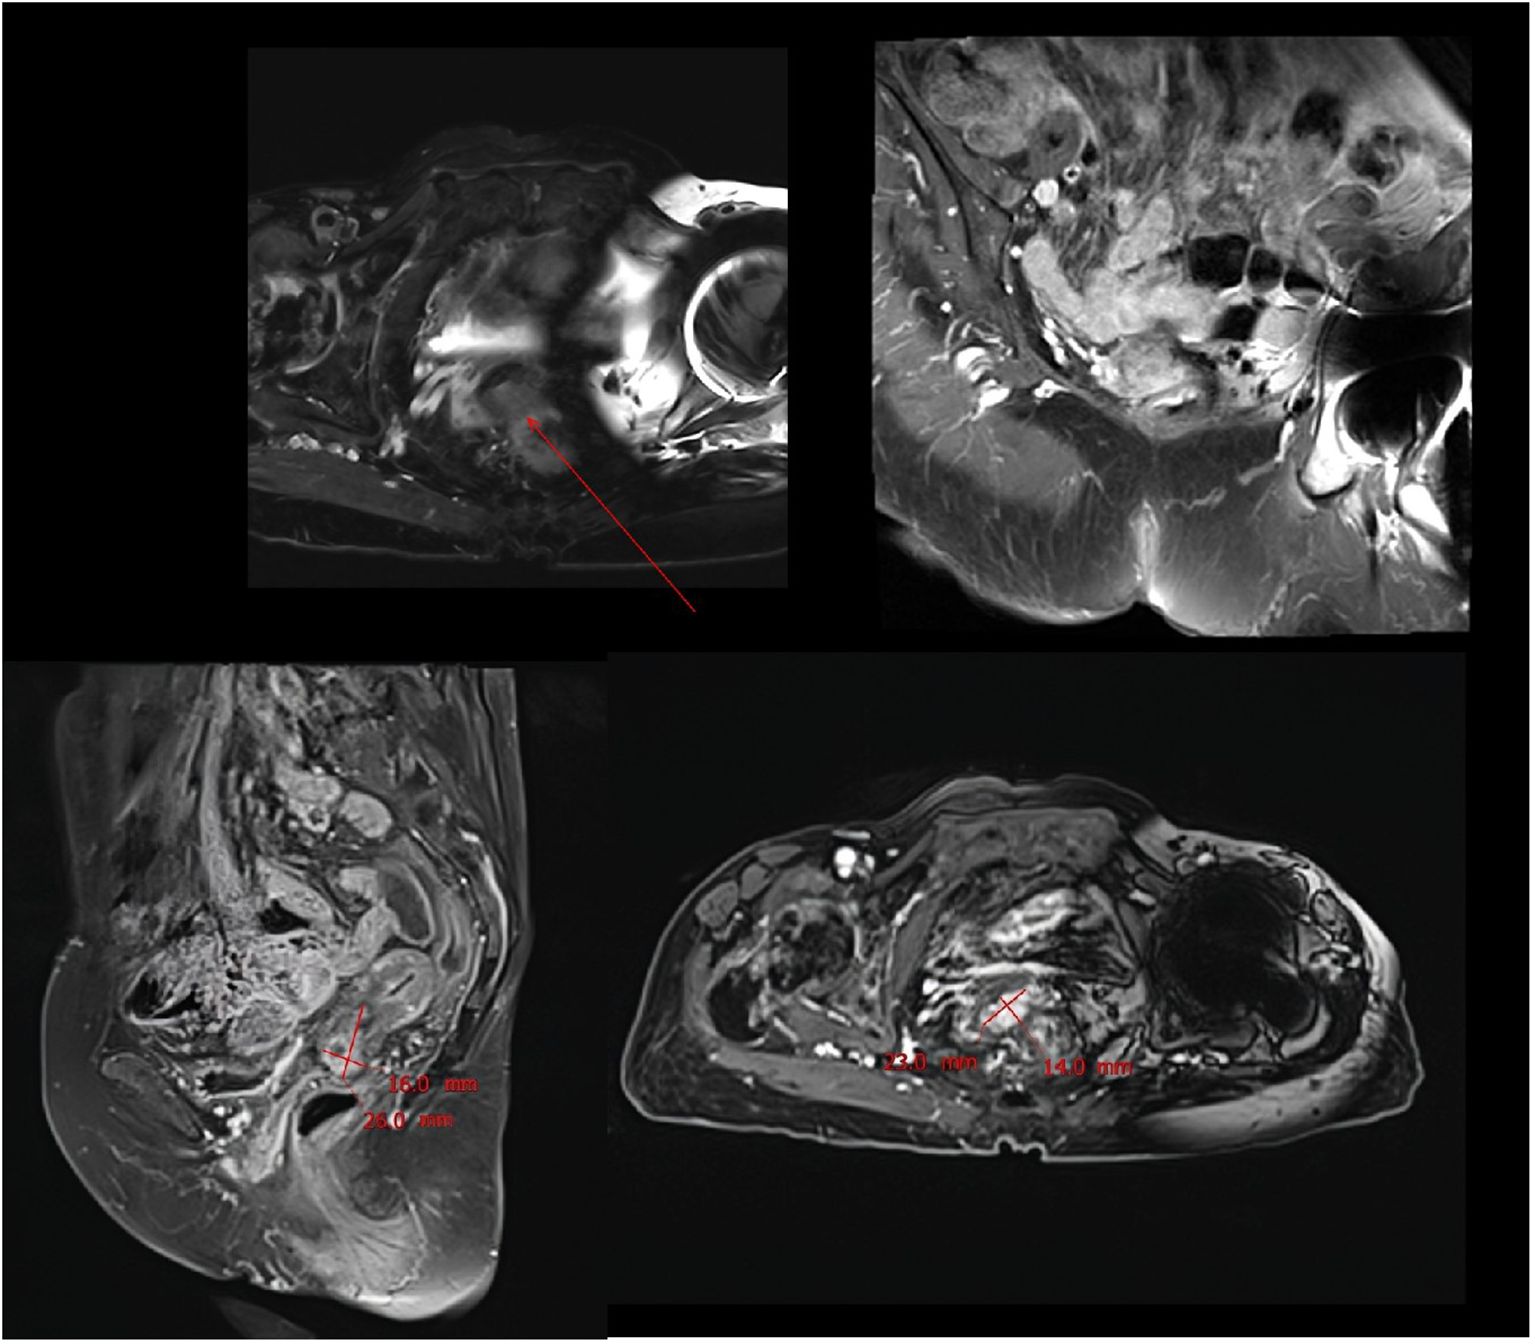

SCC is extremely rare and has a poor prognosis in advanced stage patients, with no evidence of survival benefit from radiotherapy and chemotherapy. We advised the patient to undergo genetic testing to identify potential therapeutic targets that could inform a more personalized treatment approach. The genetic testing of the patient’s tumor tissue revealed the following mutations and characteristics (1): Somatic tumor mutations:An NRAS Q61K mutation was detected at a frequency of 6%;A BRAF G464E mutation was identified at a frequency of 6.9%;An ABL1 K609del mutation was identified at a frequency of 6.0%; A DNMT3A S129G mutation was identified at a frequency of 48.2%; An EPCAM A82G mutation was identified at a frequency of 48.8%; A PALB2 A38G mutation was identified at a frequency of 42.5% (2). The tumor’s Combined Positive Score (CPS) for PD-L1 expression was 45, indicating positive programmed death-ligand 1 (PD-L1) expression (Figure 4) (3). No genes associated with hyperprogressive disease (HPD) were found (4). No mutations were detected in either immunotherapy-positive associated genes (MMR-related genes, POLE, POLD1, DDR genes, KRAS, TP53) or immunotherapy-negative associated genes (B2M, DNMT3A, JAK1/2, ALK, ROS1, MET, VEGFA, PTEN, STK11) (5). The microsatellite instability (MSI) testing results indicate a microsatellite stable (MSS) status, with an MSI score of 0.0235 (values ≥0.4 classified as MSI-H, <0.4 as MSS). The CPS for PD-L1 expression indicates that the tumor is highly likely to be sensitive to ICIs, which could make immunotherapy a viable treatment option. Prior to initiating formal antitumor therapy, the patient underwent comprehensive biochemical testing. The baseline characteristics upon hospital admission are detailed in Table 1. As a result, the patient was administered a combination therapy consisting of bevacizumab (300 mg) plus pembrolizumab (200 mg) Q3W. After 2 cycles of the therapeutic regimen, the tumor shrank significantly, and the patient did not experience any side effects(Figure 1B). Since then, the patient has continued to receive the regimen and the tumor has continued to shrink. Ultimately, after completing 10 cycles of treatment with ICIs and anti-angiogenic drugs, the positron emission tomography/computed tomography (PET-CT) scan showed complete disappearance of the tumor, with no evidence of residual cancer in the body(Figure 5). Considering the patient’s advanced stage and the high malignancy of cervical sarcomatoid carcinoma, which is highly prone to recurrence, we continued with the original treatment plan for maintenance therapy. During the maintenance therapy period, the patient underwent regular follow-up evaluations without evidence of recurrence. Treatment was maintained for 13 months until MRI demonstrated recurrence (Figure 6). Subsequently, the patient was transferred to the Department of Radiotherapy in our hospital and began radiotherapy. We still conducted regular follow-ups for the patient. Given the extremely high malignancy of this rare tumor, although the tumor eventually recurred unfortunately, the combination therapy initially achieved a transient recurrence-free survival period. Moreover, no significant adverse reactions were observed during the drug treatment. Radiotherapy was discontinued after 3 months due to concurrent tumor progression observed during treatment. The patient is currently receiving palliative care only. Our data demonstrate a progression-free survival (PFS) exceeding 13 months and overall survival (OS) surpassing 22 months.

Figure 6. MRI scan performed after 13 months of combination therapy showed significant tumor recurrence.

During the maintenance therapy period, the patient received regular follow-up evaluations, with no signs of recurrence detected. This condition persisted until 13 months after combination therapy, when MRI indicated tumor recurrence. (Figure 6). Since this disease is a rare tumor with no established treatment guidelines available, we referred to the management guidelines for cervical cancer and consulted a radiation oncologist for evaluation (23). Considering the patient’s advanced age and frail condition, the decision was made to refer her to the Department of Radiotherapy for the initiation of radiotherapy. The patient was then followed up regularly. Despite the eventual recurrence, we still consider this case a success worthy of reporting, as the patient achieved a PFS of over 13 months and an OS of over 22 months with the first-line combined treatment regimen. The success of this case suggests that for elderly and frail patients, traditional chemotherapy and radiotherapy may pose significant risks and side effects. In such scenarios, targeted therapy, being a relatively milder treatment modality, could potentially be a more suitable option for administering the care for these individuals.